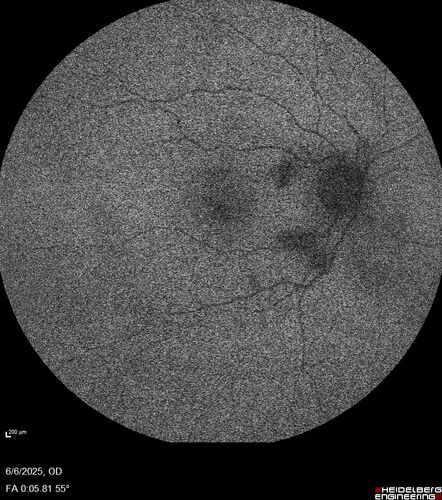

Cotton Wool Spots following cardio-pulmonary bypass

The patient had emergency thoracotomy about 3 weeks ago he had an aortic dissection with a root aneurysm. It had dissected down to the iliacs. The patient had a thoracotomy and aortic valve replacement and large aortic graft.